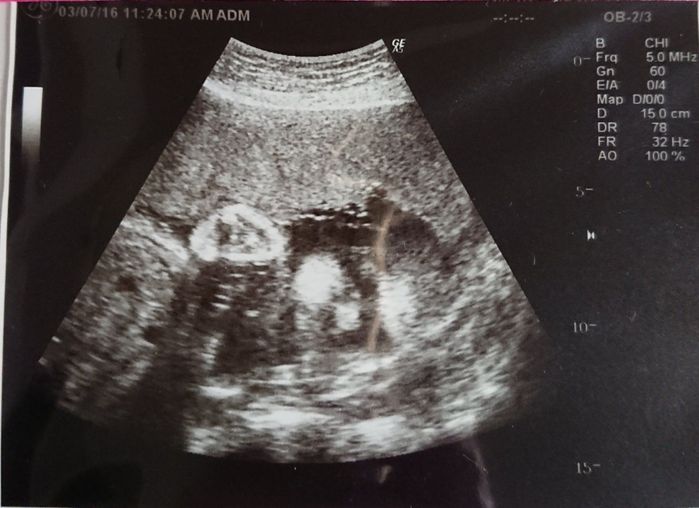

妊娠28週目 エコー写真に全身が入らないくらい大きくなりました

8ヶ月に入り、日に日に大きくなるお腹。胎動も激しくなり夜中に起きることも。仕事中に長時間立っているのがつらくなり、疲れやすくなってきました。赤ちゃんの顔がだいぶはっきりしているのが写真でわかります。